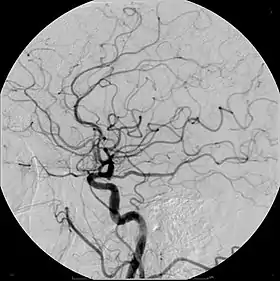

Iodinated contrast contains iodine. It is the main type of radiocontrast used for intravenous administration. Iodine has a particular advantage as a contrast agent for radiography because its innermost electron ("k-shell") binding energy is 33.2 keV, similar to the average energy of x-rays used in diagnostic radiography. When the incident x-ray energy is closer to the k-edge of the atom it encounters, photoelectric absorption is more likely to occur. Its uses include:

- Angiography (arterial investigations)